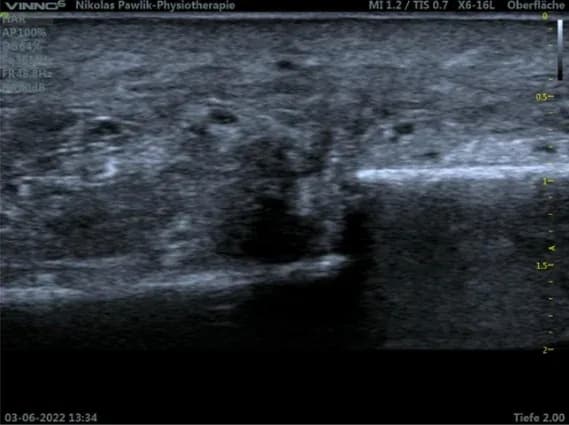

Gesunder Muskel

Diese Abbildung zeigt das Bild eines gesunden Wadenmuskels.